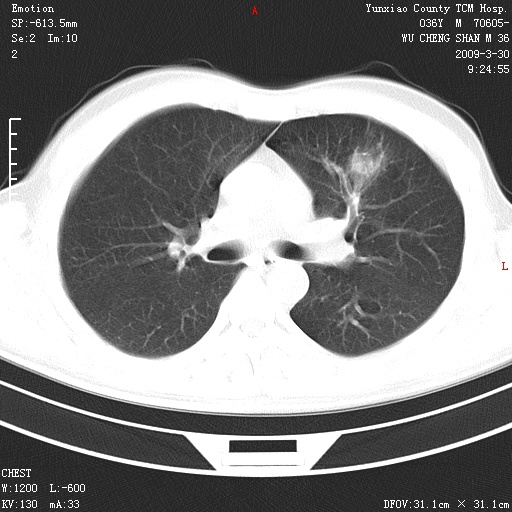

本院家属,胸痛,无咳嗽咳痰发烧病史,治疗一个月后病灶无明显改变,支气管镜示左肺慢性炎症,未见癌细胞,

胸痛,无咳嗽咳痰发烧病史,治疗一个月后病灶无明显改变,支气管镜示左肺慢性炎症,未见癌细胞,左肺下叶前段片状影,边缘不清,内见空支气管征,纵隔未见淋巴结肿大,周围无卫星灶,应考虑为炎性病变。

胸痛,无咳嗽咳痰发烧病史,治疗一个月后病灶无明显改变,支气管镜示左肺慢性炎症,未见癌细胞,左肺舌叶片状影,边缘不清,内见空支气管征,周围无卫星灶,应考虑为炎性病变。

左肺舌叶片状影,边缘不清,内见空支气管征,炎性病变